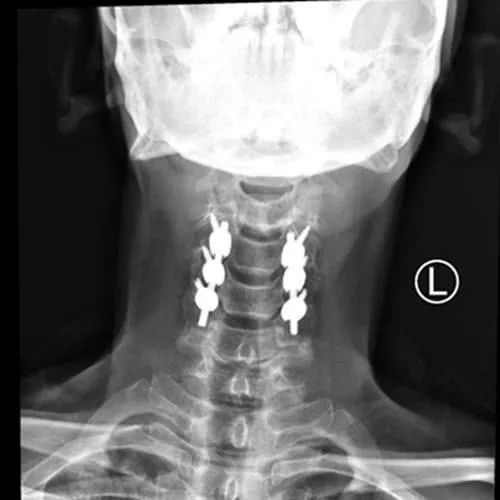

颈椎手术后复查 术后已经3个月了,感觉良好,最近几天刚把颈托摘了,目前右手还有些麻,右边身体对温度感知

颈椎病在手术后有复发的可能,但是复发率与个人的生活习惯密切相关。还有所有影像学的片子,包括术后复查的

颈椎病患者术后复查一般需要做一些常规临床体检,如肌肉的力量,病理反射等。可以比较好地判断手术后的效果

颈椎病手术后复查需要做哪些检查 多久复查一次比较好 颈椎病手术后复查需要做哪些检查

颈椎病手术后多久来复查一次?一般建议患者术后第一年之内复查还有所有影像学的片子,包括术后复查的片子。